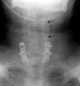

Cervical spine fusion

Anterior cervical discectomy and fusion (ACDF) is a surgical procedure to treat nerve root or spinal cord compression by decompressing the spinal cord and nerve roots of the cervical spine with a discectomy, followed by inter-vertebral fusion to stabilize the corresponding vertebrae. This procedure is used when other non-surgical treatments have failed. [Source: Wikipedia ]